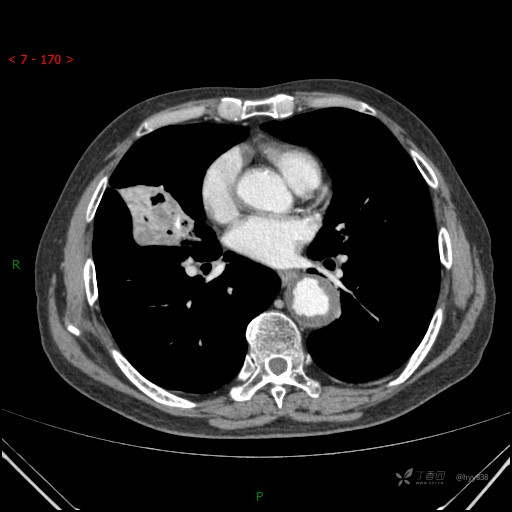

增强动脉期